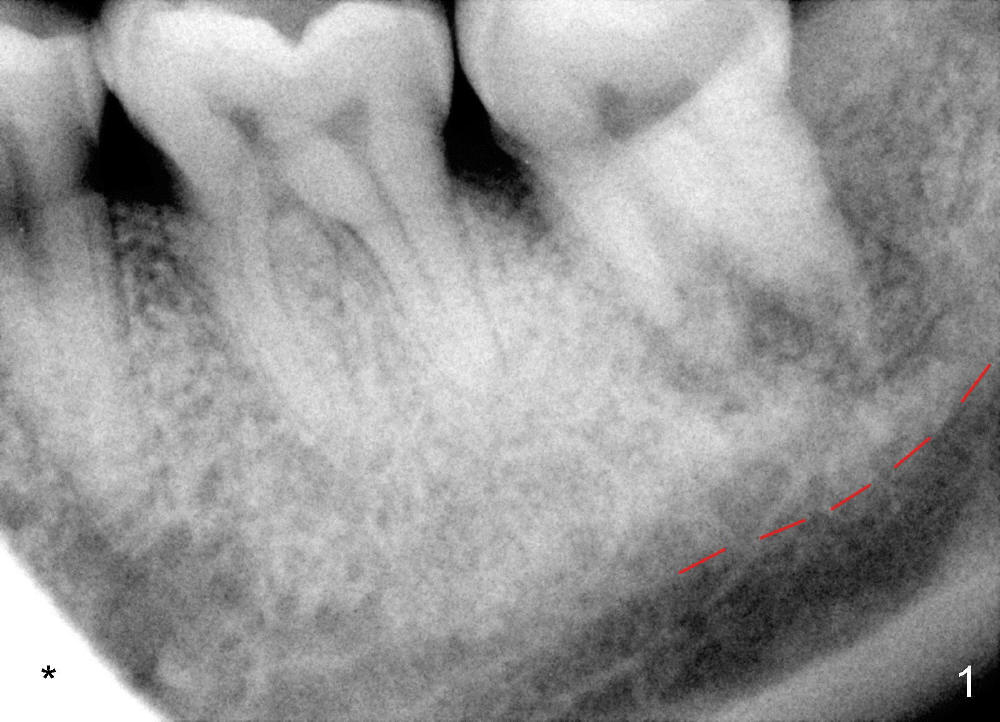

The lower left 2nd molar of a 45-year-old lady has perio-endo disease (Fig.1). The patient is not only very nervous, but also active in gag reflex. It is difficult to take good preop PA (Fig.1 *: ). Root canal therapy is performed. A relatively good PA is taken 1 year postop, again due to gap reflex (Fig.2). The tooth is still nonsalvageable (Fig.3). The last PA is taken 3.5 years before extraction and immediate implant. Infiltration anesthesia is administrated first. The patient experiences pain during early stage of osteotomy, but she does not report readily. Block anesthesia is added. Intraop PAs are taken with difficulty (Fig.4,5 with #1 sensor; 5 mm tap in place). Invasion of the inferior alveolar canal is not noted (Fig.5 dashed line). Oozing is a little more than expected. This is ignored. A 7x14 mm tapered implant is placed; the upper border of the inferior alveolar canal is not intact (Fig.6). Paresthesia area is defined next day (Fig.7). The implant is reversed for a few turns. Paresthesia area is reduced 19 days later (Fig.8). The implant is not stable. Follow up PAs are taken with difficulty (Fig.9-11). It appears that a shorter cylindrical implant is more appropriate for this case (Fig.11). The implant is stabilized with splinting with questionable result (Fig.12).